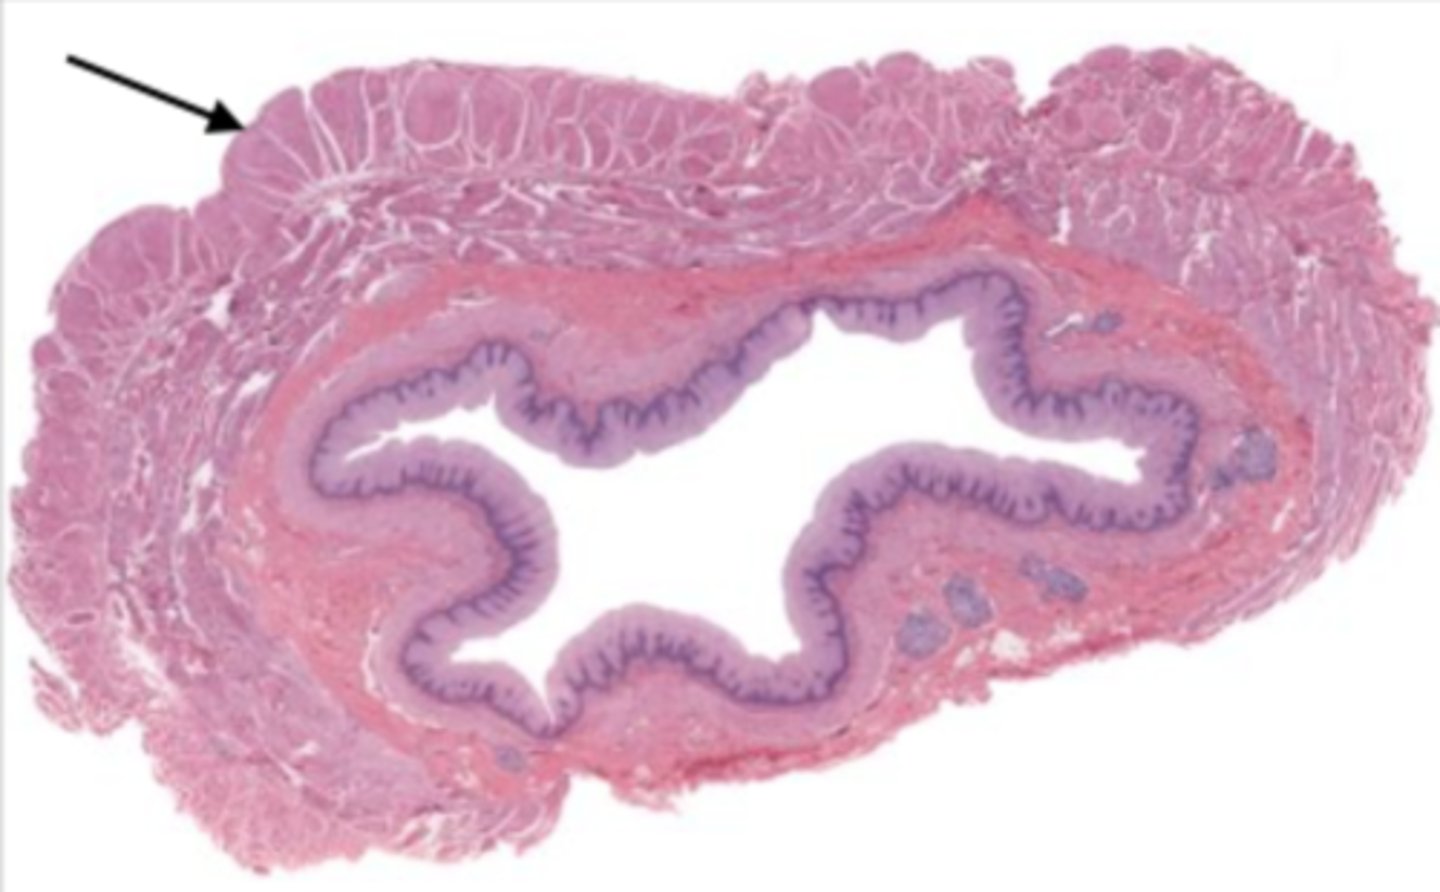

jejunum (histology)

villi (jejunum)

intestinal crypts (jejunum)

lumen (jejunum)

mucosa (jejunum)

mucosal epithelium (jejunum)

lamina propria (jejunum)

muscularis mucosa (jejunum)

submucosa (jejunum)

contains glands and blood supply

muscularis externa (jejunum)

serosa/adventitia (jejunum)